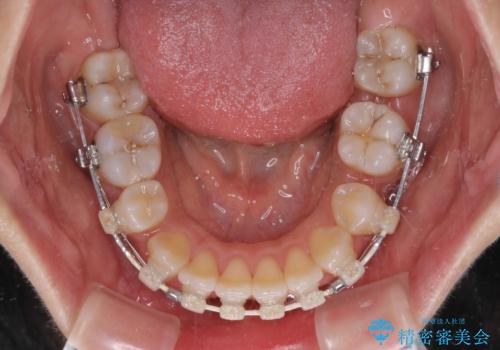

- 矯正装置

- ハーフリンガル

ハーフリンガルは、通常では表側のワイヤー矯正よりも治療期間がかかります。特に今回のように下顎左側をイレギュラーの第二小臼歯抜歯としたため、さらに時間がかかることが予想されました。

実際に治療をおこなってみると、2年を切る短期間で治療を終えることができました。